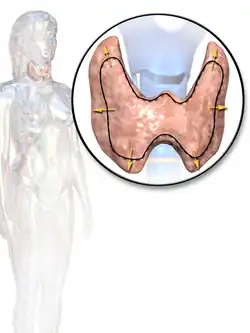

Goitre (hyperthyroidism) -

Illustration depicting enlarged thyroid that may be associated with hyperthyroidism